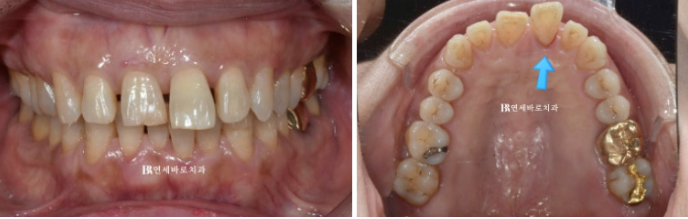

오늘은 60대 환자분이 6개월 만에 인비절라인으로 벌어진 치아를 말끔하게 교정하신 사례를 소개하겠습니다.

23.01

치아 벌어짐 증상으로 오시는 경우 단기간에 급속도로 벌어졌다면 노화가 아닌 잇몸 염증 때문인 경우가 많습니다.

특히 사진처럼 염증이 있는 치아는 점점 앞으로 돌출이 될 뿐 아니라 아래로도 내려옵니다.

그래서 벌어짐의 이유가 잇몸 염증 때문이라면 교정 치료 전 잇몸 염증 치료를 먼저 해야합니다.

그래야 치아 교정을 하면서 치아를 움직일 때의 부작용이 적습니다.

교정 후 다시 벌어지는 재발 위험도 낮출 수 있습니다.

꼼꼼히 잇몸 치료 후 인비절라인 교정 치료에 들어갔습니다.